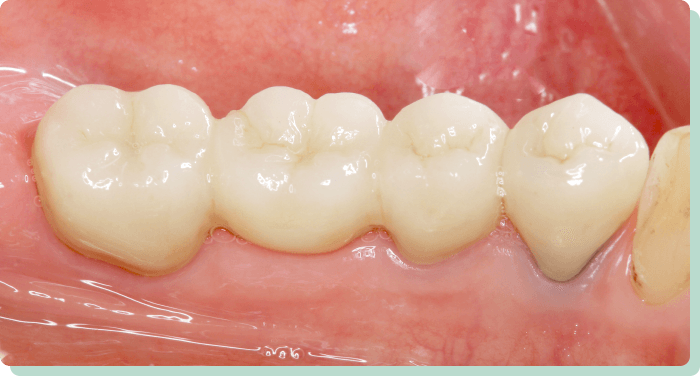

向かって右奥は3本の歯が失われています。入れ歯にすると、バネをかける歯に負担がかかり予後に不安があるだけでなく、満足な咀嚼も期待できません。インプラントを応用することにより、左右でしっかり噛めるようになりました。また、条件が許せば2本のインプラントで対応することも可能です。向かって左側は、見た目の改善を目的にセラミック4本で対応しています。

リスク:疼痛・咬合時痛・冷水痛・出血・インプラント手術による歯ぐきなどの損傷・インプラント周囲炎など

費用:インプラント治療(計3本):1,320,000円

セラミック治療(計4本):350,000円